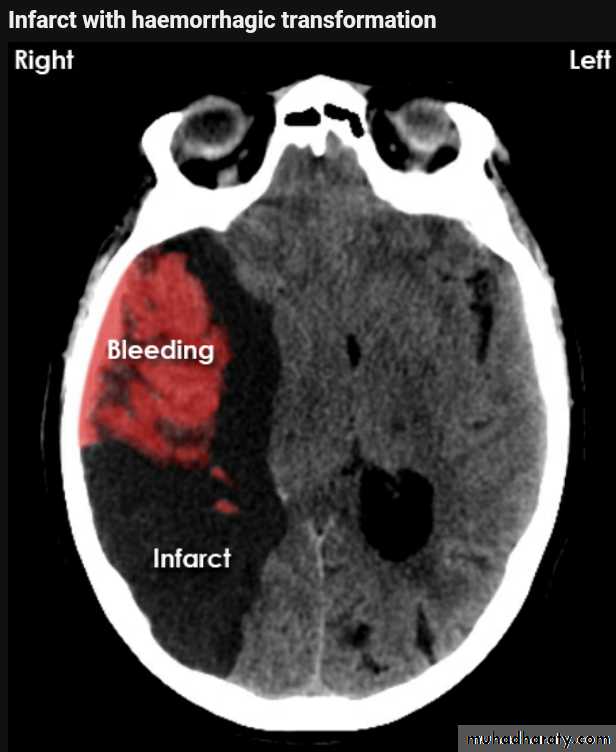

Infarction

AcuteChronic

Acute infarction

Wedge shape area of hypo density involve the tributaries of anterior , middle or posterior cerebral arteries , ( i.e. priato frontal &priato occipital area )

Dense middle artery sign

* wedge shape hypo density area.* Shifting of the midline & frontal horn

Chronic infarction

Hypo density area(pore encephalic cyst)Dilated ventricle